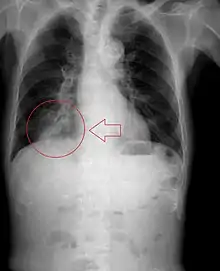

Radiography is the most common form of imaging used in the initial assessment of a foreign body presentation. Most patients receive a chest x-ray to determine the location of the foreign body.[2] Lateral neck, chest, and bilateral decubitus end-expiratory chest x-rays should be obtained in patients suspected of having aspirated a foreign body.[6] However, the presence of normal findings on chest radiography should not rule out foreign body aspiration as not all objects can be visualized.[2] In fact, up to 50% of cases can have normal findings on radiography.[7] This is because visibility of an object depends on many factors, such as the object's material, size, anatomic location and surrounding structures, as well as the patient's body habitus.[13] X-ray beams only show an object if that object's composition blocks the rays from traveling through, making it radiopaque and appearing lighter or white on the image. This also requires it to not be stuck behind something that blocks the beams first.[13] Objects that are radiopaque include items made of most metals except aluminum, bones except most fish bones, and glass. If the material does not block the x-ray beams it is considered radiolucent and will appear dark which prevents visualization.[13] This includes material such as most plastics, most fish bones, wood, and most aluminum objects.[13]

Signs on x-ray that are more commonly seen than the object itself and can be indicative of foreign body aspiration include visualization of the foreign body or hyperinflation of the affected lung.[13] Other x-ray findings that can be seen with foreign body aspiration include obstructive emphysema, atelectasis, and consolidation.[8]